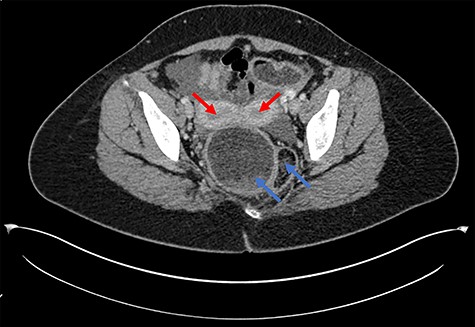

A 28-year-old woman presented to the emergency department with a 1-week history of abdominal pain, bloating and constipation. A computed tomography (CT) scan was performed, which demonstrated distension and a lead pipe appearance of the right colon suggesting a mild colitis (Fig. 1). The CT scan also demonstrated a duplicated segment of colon with a blind ending proximal limb (Figs 1 and 2), uterine didelphys (Fig. 2) and a duplicated bladder (Fig. 3). A subsequent magnetic resonance imaging scan demonstrated an 11 cm segment of thickened bowel with mucosal ulceration and surrounding hyperaemia confined to the duplicated colon. Sigmoidoscopy was performed and histology from the duplicated descending colon demonstrated mild active chronic colitis with crypt inflammation and associated abscesses without granuloma formation. The native colon had an unremarkable appearance. The patient was started on mesalazine and has had no further complaints of abdominal pain or bloating.

Axial CT scan demonstrating uterine didelphys (red arrows) and duplicated rectum (blue arrows).